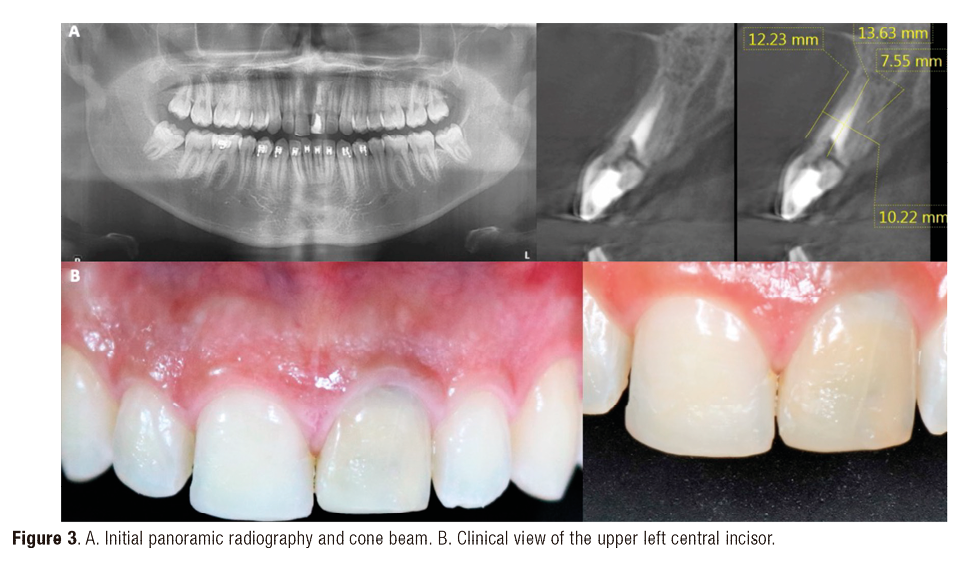

A 24-year-old male patient who required extraction of the upper left central incisor due to a corono-radicular fracture, reason for which is requested, panoramic radiography and cone beam, in which, as in the immediately previous case, the extraction was planned using a two-armed lever as an atraumatic alveolar preservation technique. During the clinical examination, it was observed at the level of the upper left central incisor, resin filling of 4 surfaces and slight redness was evident at the gingival margin (Figure 3.A and Figure 3.B). The extraction procedure was initiated by applying the strength of the two-arm lever, the straight elevator is in a horizontal position resting on the mesial and distal surfaces have the greatest possible palatal rest and resistance in the mesial and/or disto-vestibular areas; that generates an extrusive dental dislocation that combined with the vestibular palatine grip with the left hand helps to avoid compromising the vestibular table, then it is produced in the first instance, tooth crown extraction (Figure 4.A and Figure 4.B), by the corono-radicular fracture already mentioned, then its proceed to the dental root´s extraction, using lever of the second degree, without compromising the vestibular and palatal tables. Once confirmed the integrity of the vestibular wall and the gingival biotype: type I socket, 1cc of Puros® particulate cortical bone (250-1000 microns) is used for the graft. Subsequently, Zimmer TSV 3.7 * 13mm implant was placed (Figure 5). The implant was prepared and placed 2.5mm from the gingival margin to achieve primary fixation, a surgical cover screw was placed, the cavity was occluded with a collagen membrane (CollaTape®) and sutured transverse and horizontally with acid polyglycolic 5-0, followed by a provisional restoration, finally, the patient is prescribed oral capsules of dicloxacillin 500mg and nimesulide tablets orally 100mg. After five months of clinical and radiographic controls, the second phase begins. The patient received a metallic ceramic crown with functional and aesthetic results after 18 months of continuous controls.